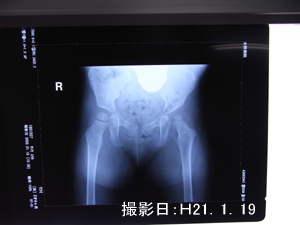

装具をはずしてすぐのレントゲン(1/19)ではあまり空いていないのに

6/15撮影では空いているのがわかります

この隙間をなくさないといけないみたいです